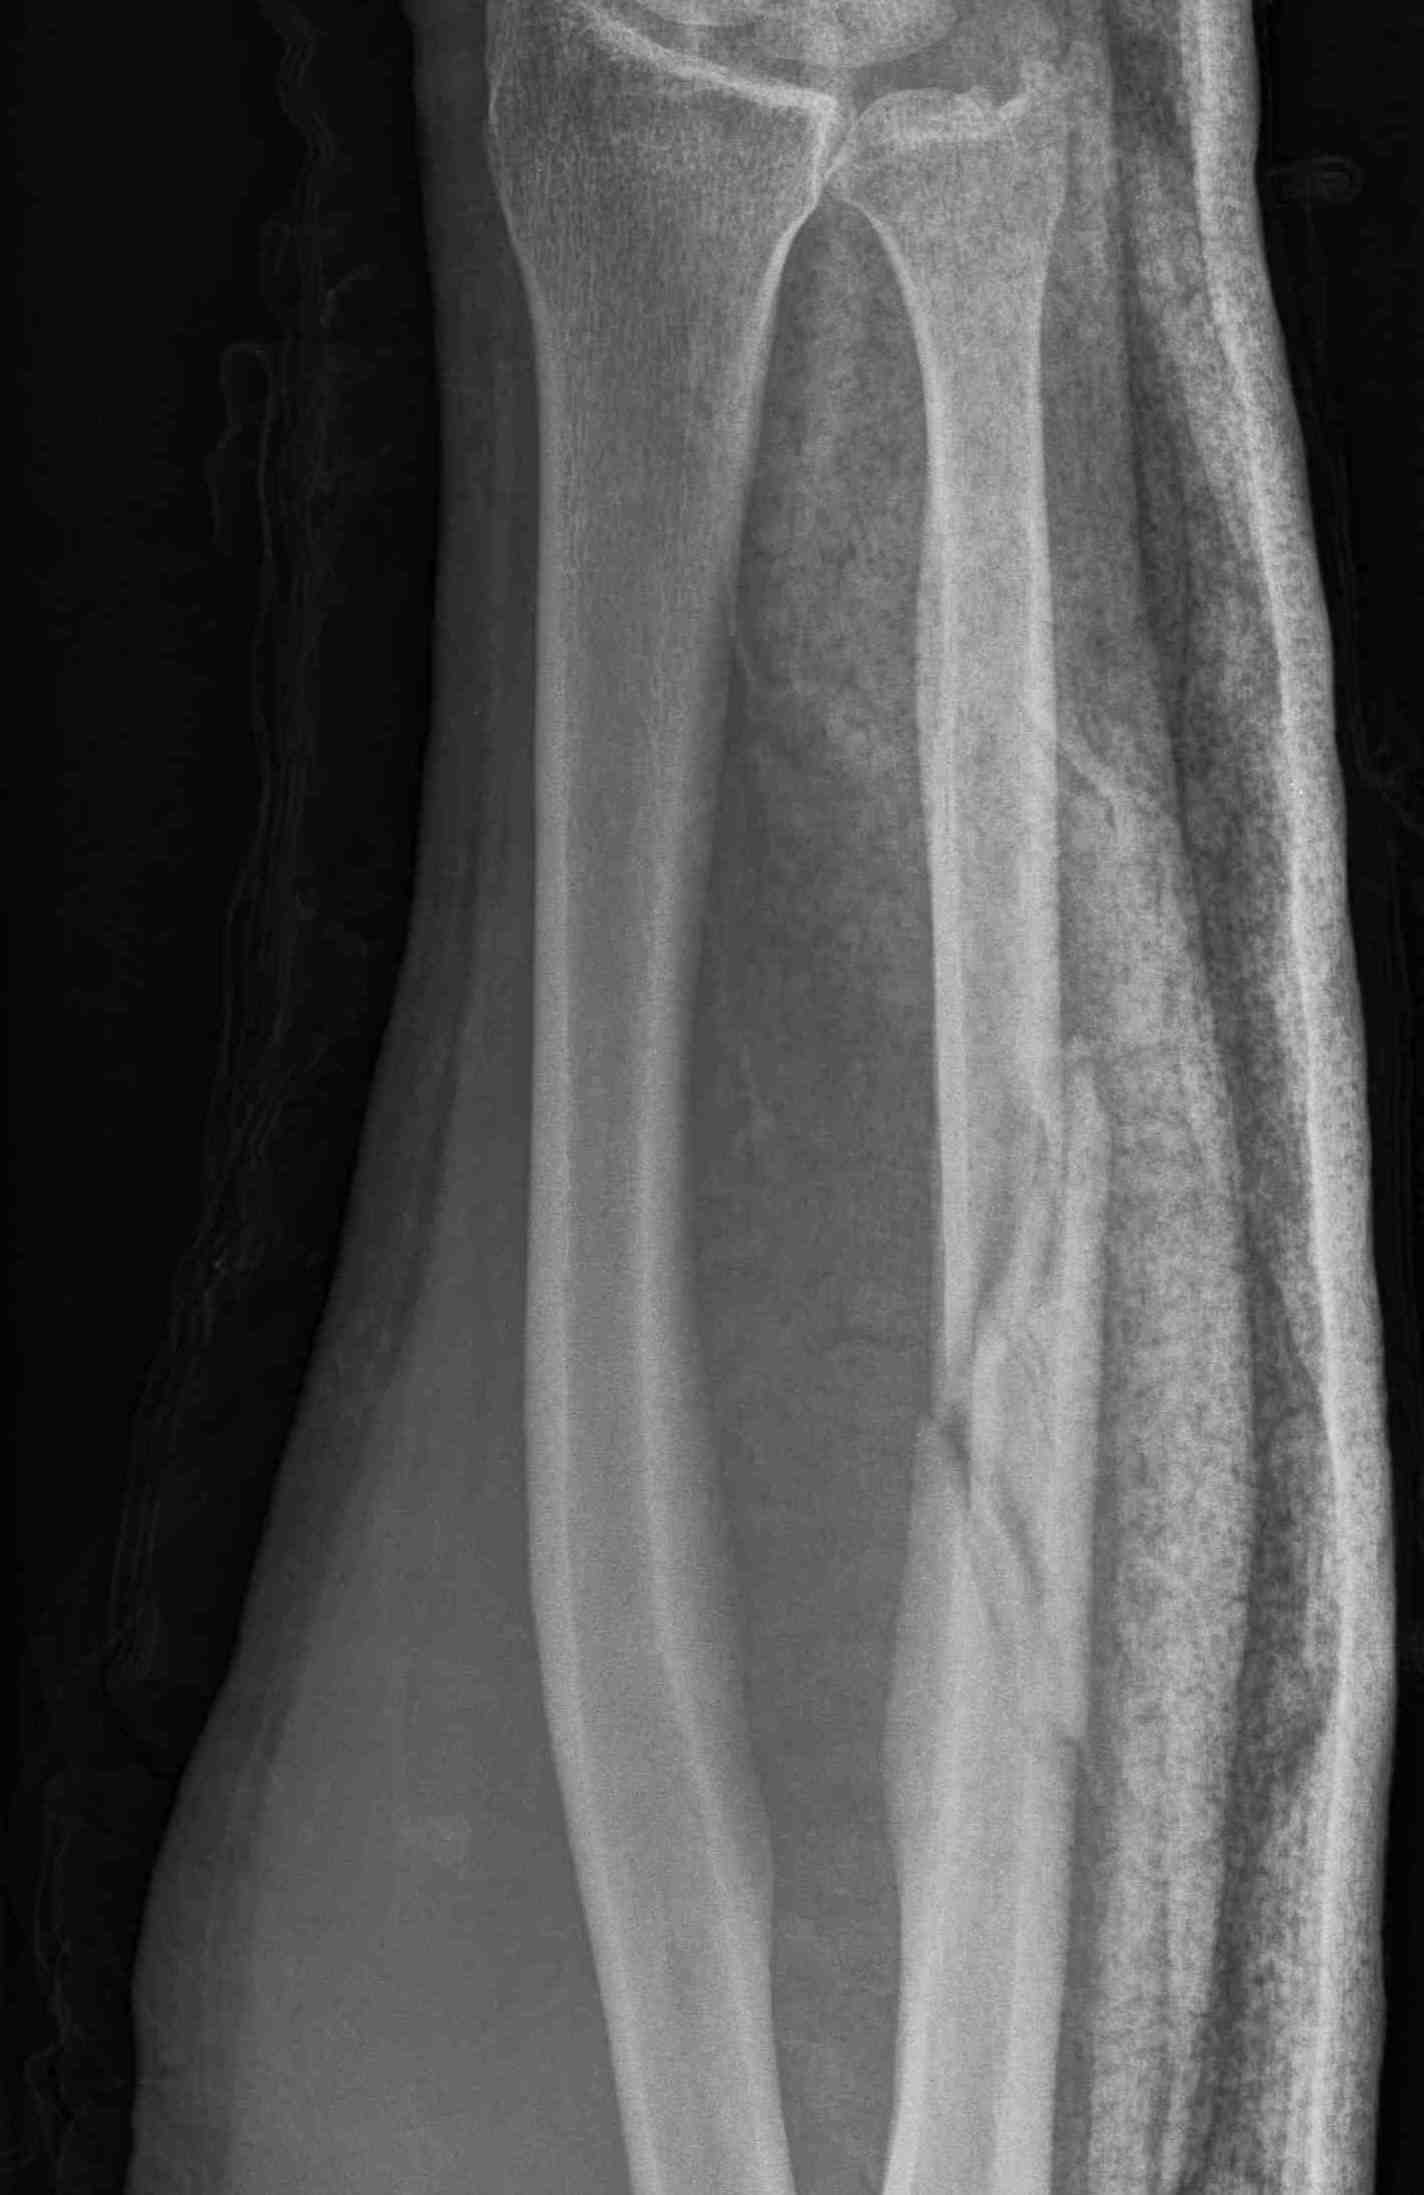

Proximal - beware Monteggia / radial head dislocation

Ulna nonunion after plating

Nonunions

Results

- IM K wire v plate in 54 patients

- 3 nonunions with plate, none with IM wire

- 70% of patients required wire removal

- 11% of patients required plate removal